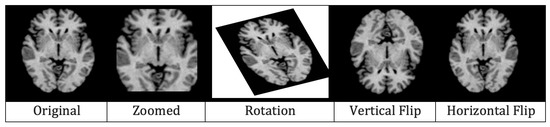

4.2.6. Augmentation